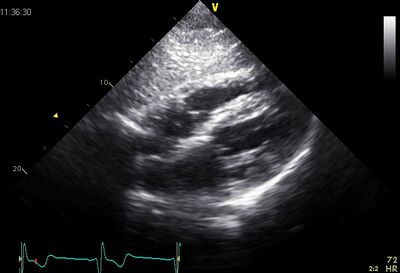

Echocardiographic views

Plax by tilted PSax Ao

AP4CH Subcostal